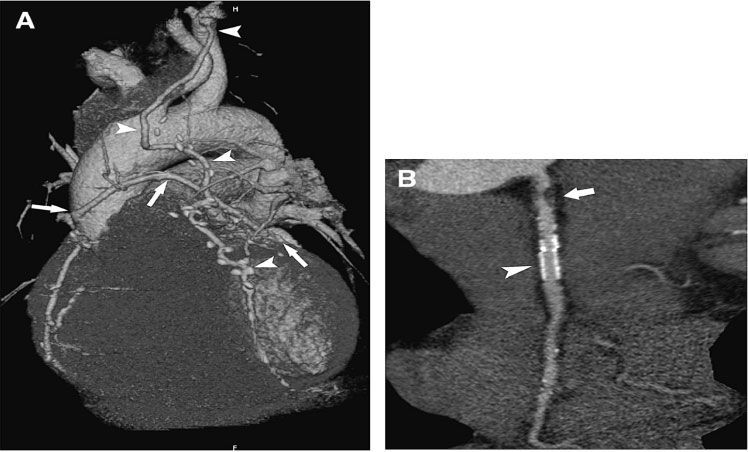

Визуализация атеросклеротического поражения коронарных артерий с помощью МСКТ является альтернативой инвазивной коронарографии (КАГ) (рис № 5) и используется как при доказанной ИБС [2,3,12,40], при подозрении на ИБС, так и у асимптоматических больных [2,14,67] с целью диагностики, выявления групп риска и определения их дальнейшего прогноза.

![]() |

| Рис.5. КАГ (E, F) и МСКТ коронарных артерий( A, B, C, D). Гемодинамически значимый стеноз ПКА (стрелки). |

Большое число исследований, посвященных данному вопросу, показали, что 64 мультиспиральная КТ коронарных артерий при диагностике гемодинамически значимого стенотического поражения (стеноз >=50%) имеет в сравнении с КАГ: чувствительность 94%-100%, специфичность 95%- 97%, положительную предсказательную ценность 87%-97%, отрицательную предсказательную ценность 99%-100% [3,20,23,30,35,47,48]. Приведенные результаты подтвердили идентичность получаемых результатов МСКТ и КАГ в диагностике атеросклероза венечных артерий (рис. №5,42).